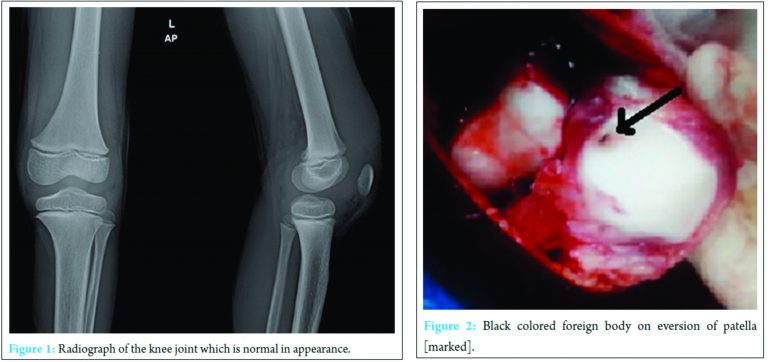

Routine blood examination was done, and the result was elevated total count (16.1×103), differential count (polymorphs – 73%, lymphocytes – 20%, and basophile – 07%). Erythrocyte sedimentation rate was – 28 mm/h and C-reactive protein positive. Hemoglobin was – 10.3 g/dl. Plain radiography of the left knee joint shows no obvious bony injury except for soft tissue swelling (Fig. 1). Magnetic resonance imaging (MRI) of the left knee joint was advised which was reported as extensive synovitis with effusion and thickened suprapatellar plica and multiple enlarged inguinal and popliteal lymph nodes with larges measuring 1.5 cm × 1.0 cm.

Under appropriate anesthesia after preparing, painting and draping the left knee, under tourniquet, through an anterior midline linear incision with medial parapatellar arthrotomy knee joint was opened. Seropurulent fluid was found, with extensive reactive synovitis. Near total synovectomy removing abnormal looking tissue was done specimen sent for histopathological examination. On everting the patella a black spot (Fig. 2) was noted on the articular surface on further tracing it was a foreign body appeared to be a piece of thorn and was removed. On retrospective inspection of the anterior surface of patella, an area of redness was seen appeared to be like a foreign body granuloma (Fig. 3). The tract was curetted (Fig. 4). No articular cartilage affection noticed. Through saline wash given and wound closed in layers over a negative suction draining tube. Intraoperative knee movements were found to be full.